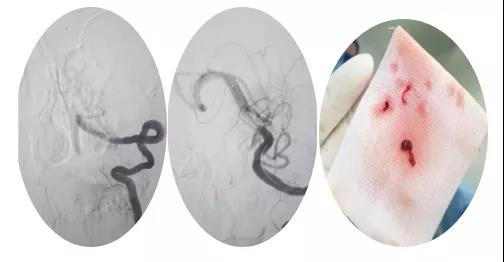

18:30手術(shù)開始,造影為基底動(dòng)脈閉塞,與患者家屬充分溝通,患者家屬同意給予介入取栓治療。共取栓2次,取出少量暗紅色血栓塊。造影示:基底動(dòng)脈有重度狹窄,結(jié)合患者病情演變及造影結(jié)果,考慮為動(dòng)脈粥樣硬化性狹窄。根據(jù)患者造影結(jié)果,目前單純?nèi)∷o(wú)法達(dá)到預(yù)期效果,決定給予基底動(dòng)脈支架植入術(shù)。根據(jù)患者基底動(dòng)脈直徑選擇3.0*13mm apollo球擴(kuò)支架,支架植入后造影示狹窄消失。

支架植入后患者神志轉(zhuǎn)清,四肢均可活動(dòng),左側(cè)肢體活動(dòng)略差于右側(cè),收入神經(jīng)內(nèi)四科病房進(jìn)一步治療。術(shù)后第三天患者神志清,四肢活動(dòng)基本正常,住院5天轉(zhuǎn)入當(dāng)?shù)蒯t(yī)院治療。?